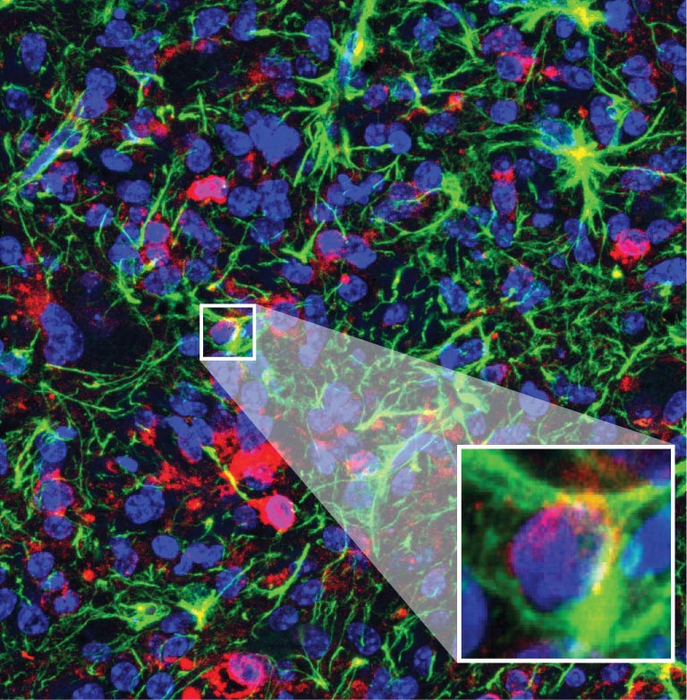

The new ASO drug works by shutting down a mutated protein called H3.3K27M. In DIPG, the dominant mutation blocks closely related proteins from turning many genes on and off. This leads to uncontrolled cell growth—cancer. When the team used the ASO drug on mice with DIPG, the genes it affected returned to normal. The tumors stopped growing as fast, and the animals lived longer.

“After treatment, the cancer looked very different,” says Krainer. “We could see a lot fewer proliferating cells, and the tumor cells were differentiating into healthy nerve cells. That tells us DIPG’s malignant changes are reversible to an extent.”